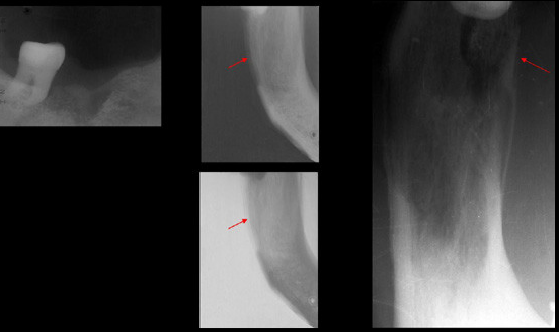

Paciente femenino 72 años de edad, acude a la consulta por presentar secresión purulenta en zona de extracción de pieza 4.6 realizada hace aproximadamente cuatro meses . En la radiografía panorámica se observa rarefacción ósea que compromete cuerpo mandibular del lado derecho con aumento de la densidad ósea circundante; en las radiografías intraorales apreciamos reacción periostal a nivel de la tabla ósea vestibular, así como la presencia de secuestro óseo hacia la tabla ósea lingual. Obsérves también la alteración en la morfología condilar bilateral compatible con proceso degenerativo articular (Osteoartrosis).